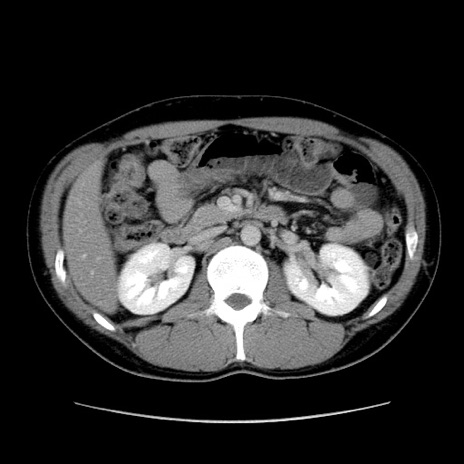

症例36(横断像)

【症例】20歳代 男性

【主訴】心窩部痛

【現病歴】今朝より上腹部痛あり。一旦軽快していたが再度出現したため救急要請。昨日夕に白身の魚を含む刺身を食べた。

【身体所見】BP 136/89mmHg、HR 74/min、BT 37.0℃、腹部:膨満、軟、心窩部に圧痛あり。反跳痛なし、筋性防御なし、腸雑音やや亢進あり。

【データ】WBC 17700、CRP 0.48